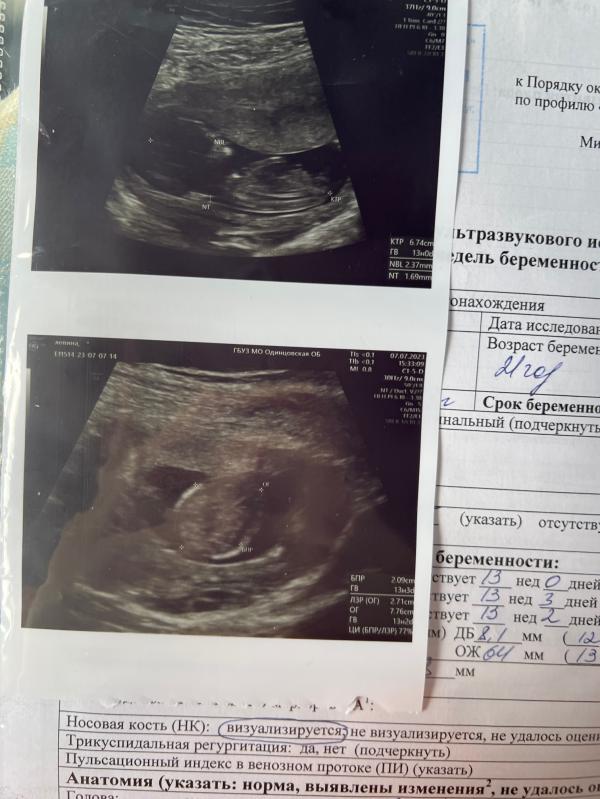

Вот и прошел мой первый триместр, мы плавно и с хорошими новостями зашли во второй! Прошли первый скрининг, бусинку не узнать, уже лицо четкое, сказали мой носик) очень рада, что мы здоровы и развиваемся как надо. Сейчас начнётся рост малыша, жду уже большого животика и конечно же 16 недель, что бы узнать кто там у нас сидит, хочется уже понимать как обращаться он или она)